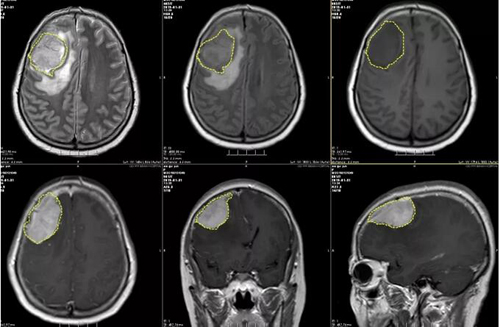

图2:术前MR示右侧额顶部占位性病变,考虑脑膜瘤可能;右侧大脑镰下疝